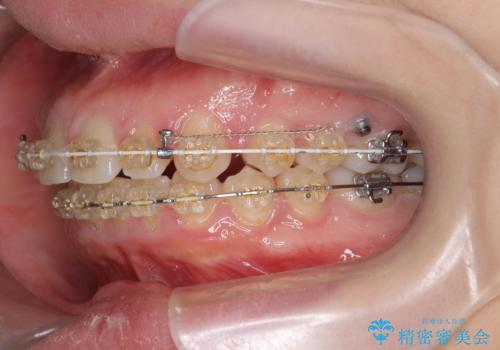

深い噛み合わせ、すきっ歯の改善 ワイヤーを用いたマルチブラケット矯正

- 矯正装置

- ワイヤー矯正

- 噛み合わせが深く、前歯が突き出て隙間が出てきたことの改善を希望され矯正治療の相談で当院に初診来院されました。

ワイヤーを用いたマルチブラケット矯正を行うことで深い噛み合わせを改善し、前歯の隙間もなくし審美的な歯列へと治療をおこなっていきます。